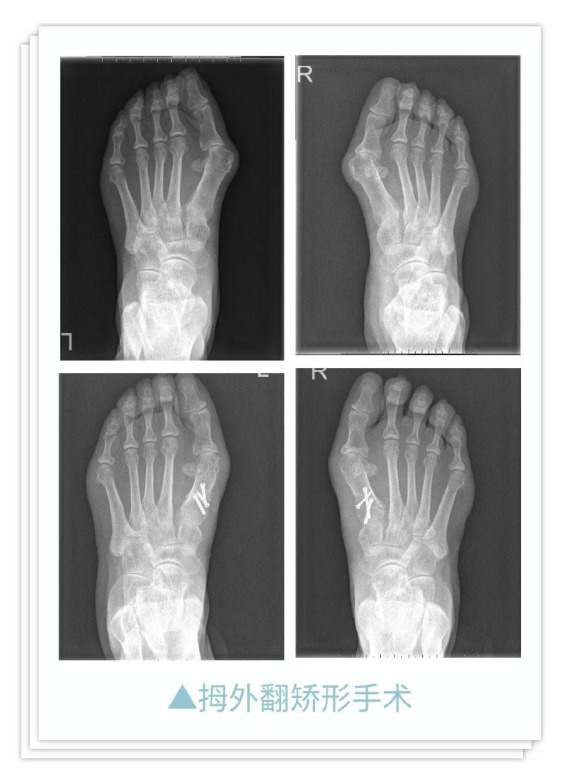

特色技术

典型病例